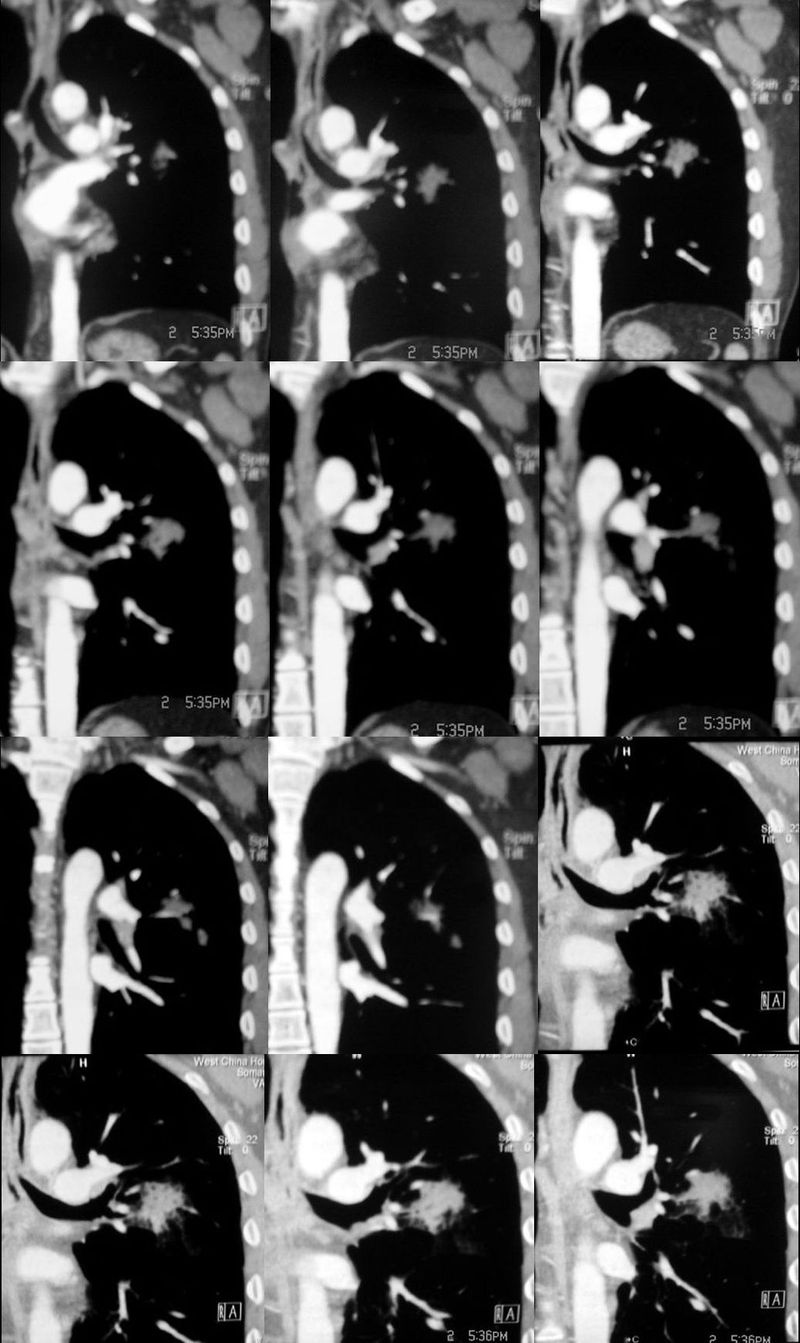

球形肺炎是大叶性肺炎的一种特殊表现[1],以肺的渗出实变为主。它的机理未明,可能是由于抗生素的广泛应用,大叶性或节段性肺炎发展受到限制而形成球形,其形成又与病缘菌的毒性数量及机体的免疫能力有关。病人多有感然症状,某些病人无明显感然症状。病变呈球形或椭圆形,大小不等,病灶密度多均匀,ct值稍低于软组织密度;或中央密度高,边缘密度低,显示晕圈状改变;有时可见空洞[2]。病灶边缘比较规则,也可不规则,有毛刺或呈锯齿状改变,但较模糊。位于肺周区,贴近胸膜,部分病栽表现为两侧缘垂直于胸膜,呈刀切样平直边缘。病灶周围血管纹理增多、增粗、常有局限性胸膜增厚。球形肺炎抗炎两周后,病灶即有缩小,最后能完全吸收。

球形肺炎:病变密度相对较淡,中央密度略高,ct图片上密度较为均匀,增强中央可出现无强化区。病变邻近胸膜反应较为显著,可表现为增厚、粘连(可以比较广泛),病变内可以见到大血管的贯穿,周围及近肺门侧可以见到血管纹理增多、增粗,可有支气管充气征象,两侧可垂直于胸膜或呈方形,边缘可为刀切征,它可以出现毛刺样的类似改变,短期内抗炎治疗有效。